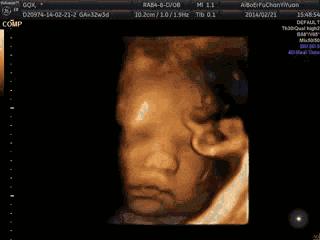

第3張圖:揉眼睛

大約20周左右,寶寶的視力已初步發育,能隱約感受到光線。因此有的胎教會建議媽媽適當曬曬太陽,或用手電筒溫和地照照肚皮。

透過羊水,寶寶能感受到微弱的光亮。有時候,他們還會自己揉揉眼睛,探索身體的小部位呢!